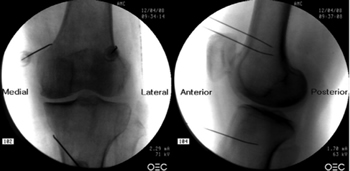

To perform a fluoroscopic-guided TRFGN, we need an anteroposterior (AP) and lateral view of the knee (Figure 2). First we place the patient in supine position with a pillow under the popliteal fossa (to make the patient more comfortable) (16). After performing asepsis and antisepsis of the knee, we proceed to locate the GN (Table II). SLGN is advancing the TFR needle toward the confluence of the lateral femoral diaphysis with the lateral femoral condyle in an AP view and at a mid-point of the femur in a lateral view. The SMGN is located by advancing the needle toward the confluence of the medial femoral diaphysis with the medial femoral condyle in an AP view and at a mid-point of the femur in a lateral view. Finally, the IMGN is located by advancing the needle toward the confluence of the medial tibial diaphysis with the tibial epicondyle in an AP view and at a midpoint of the tibia in a lateral view (16,17).

Fig. 2. Anteroposterior (AP) and lateral projection where therapeutic targets are observed using fluoroscopy. Image taken from Choi et al. (9). Reproduced with the permission of Jin Woo Shin.

Table II. Location of genicular nerves guided by fluoroscopy

Good AP and lateral view is very important. In AP projection, the tibiofemoral joint should have a similar width on both sides of the knee with the interspace open (9). In lateral projection, there must be a correct overlap of both femoral condyles to perform a satisfactory blockage of the SMGN and SLGN (18).